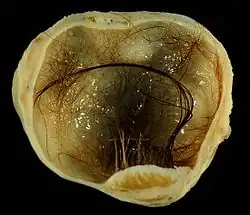

Teratocarcinoma (teratomas malignos)

Teratomas são crescimentos descontrolados de células, que geralmente são compostos de vários tecidos, como cabelos, músculos e ossos, ocorrendo com maior frequência nos ovários (mulheres) e nos testículos (homens). Quando esses teratomas são malignos, eles são chamados de teratocarcinomas, sendo considerados um tipo de câncer.[78]

Teratoma de 4 cm encontrado no ovário de uma mulher. Macroscopicamente pode ser observado cabelo e microscopicamente pode ser observado células do sistema nervoso central

Nesse tipo de câncer, o tumor não é causado por uma mutação genética, mas sim pelo ambiente externo da célula. Através de experimentos, sendo o mais famoso realizado com camundongos, observou-se que se uma massa de células é colocada no interior de um blastocisto de camundongo, ela vai se integrar ao blastocisto, perder sua malignidade e se dividir normalmente; caso contrário, se ela for colocada em uma outra região, isso pode levar à formação do teratocarcinoma, tornando-se um tumor maligno.[78]